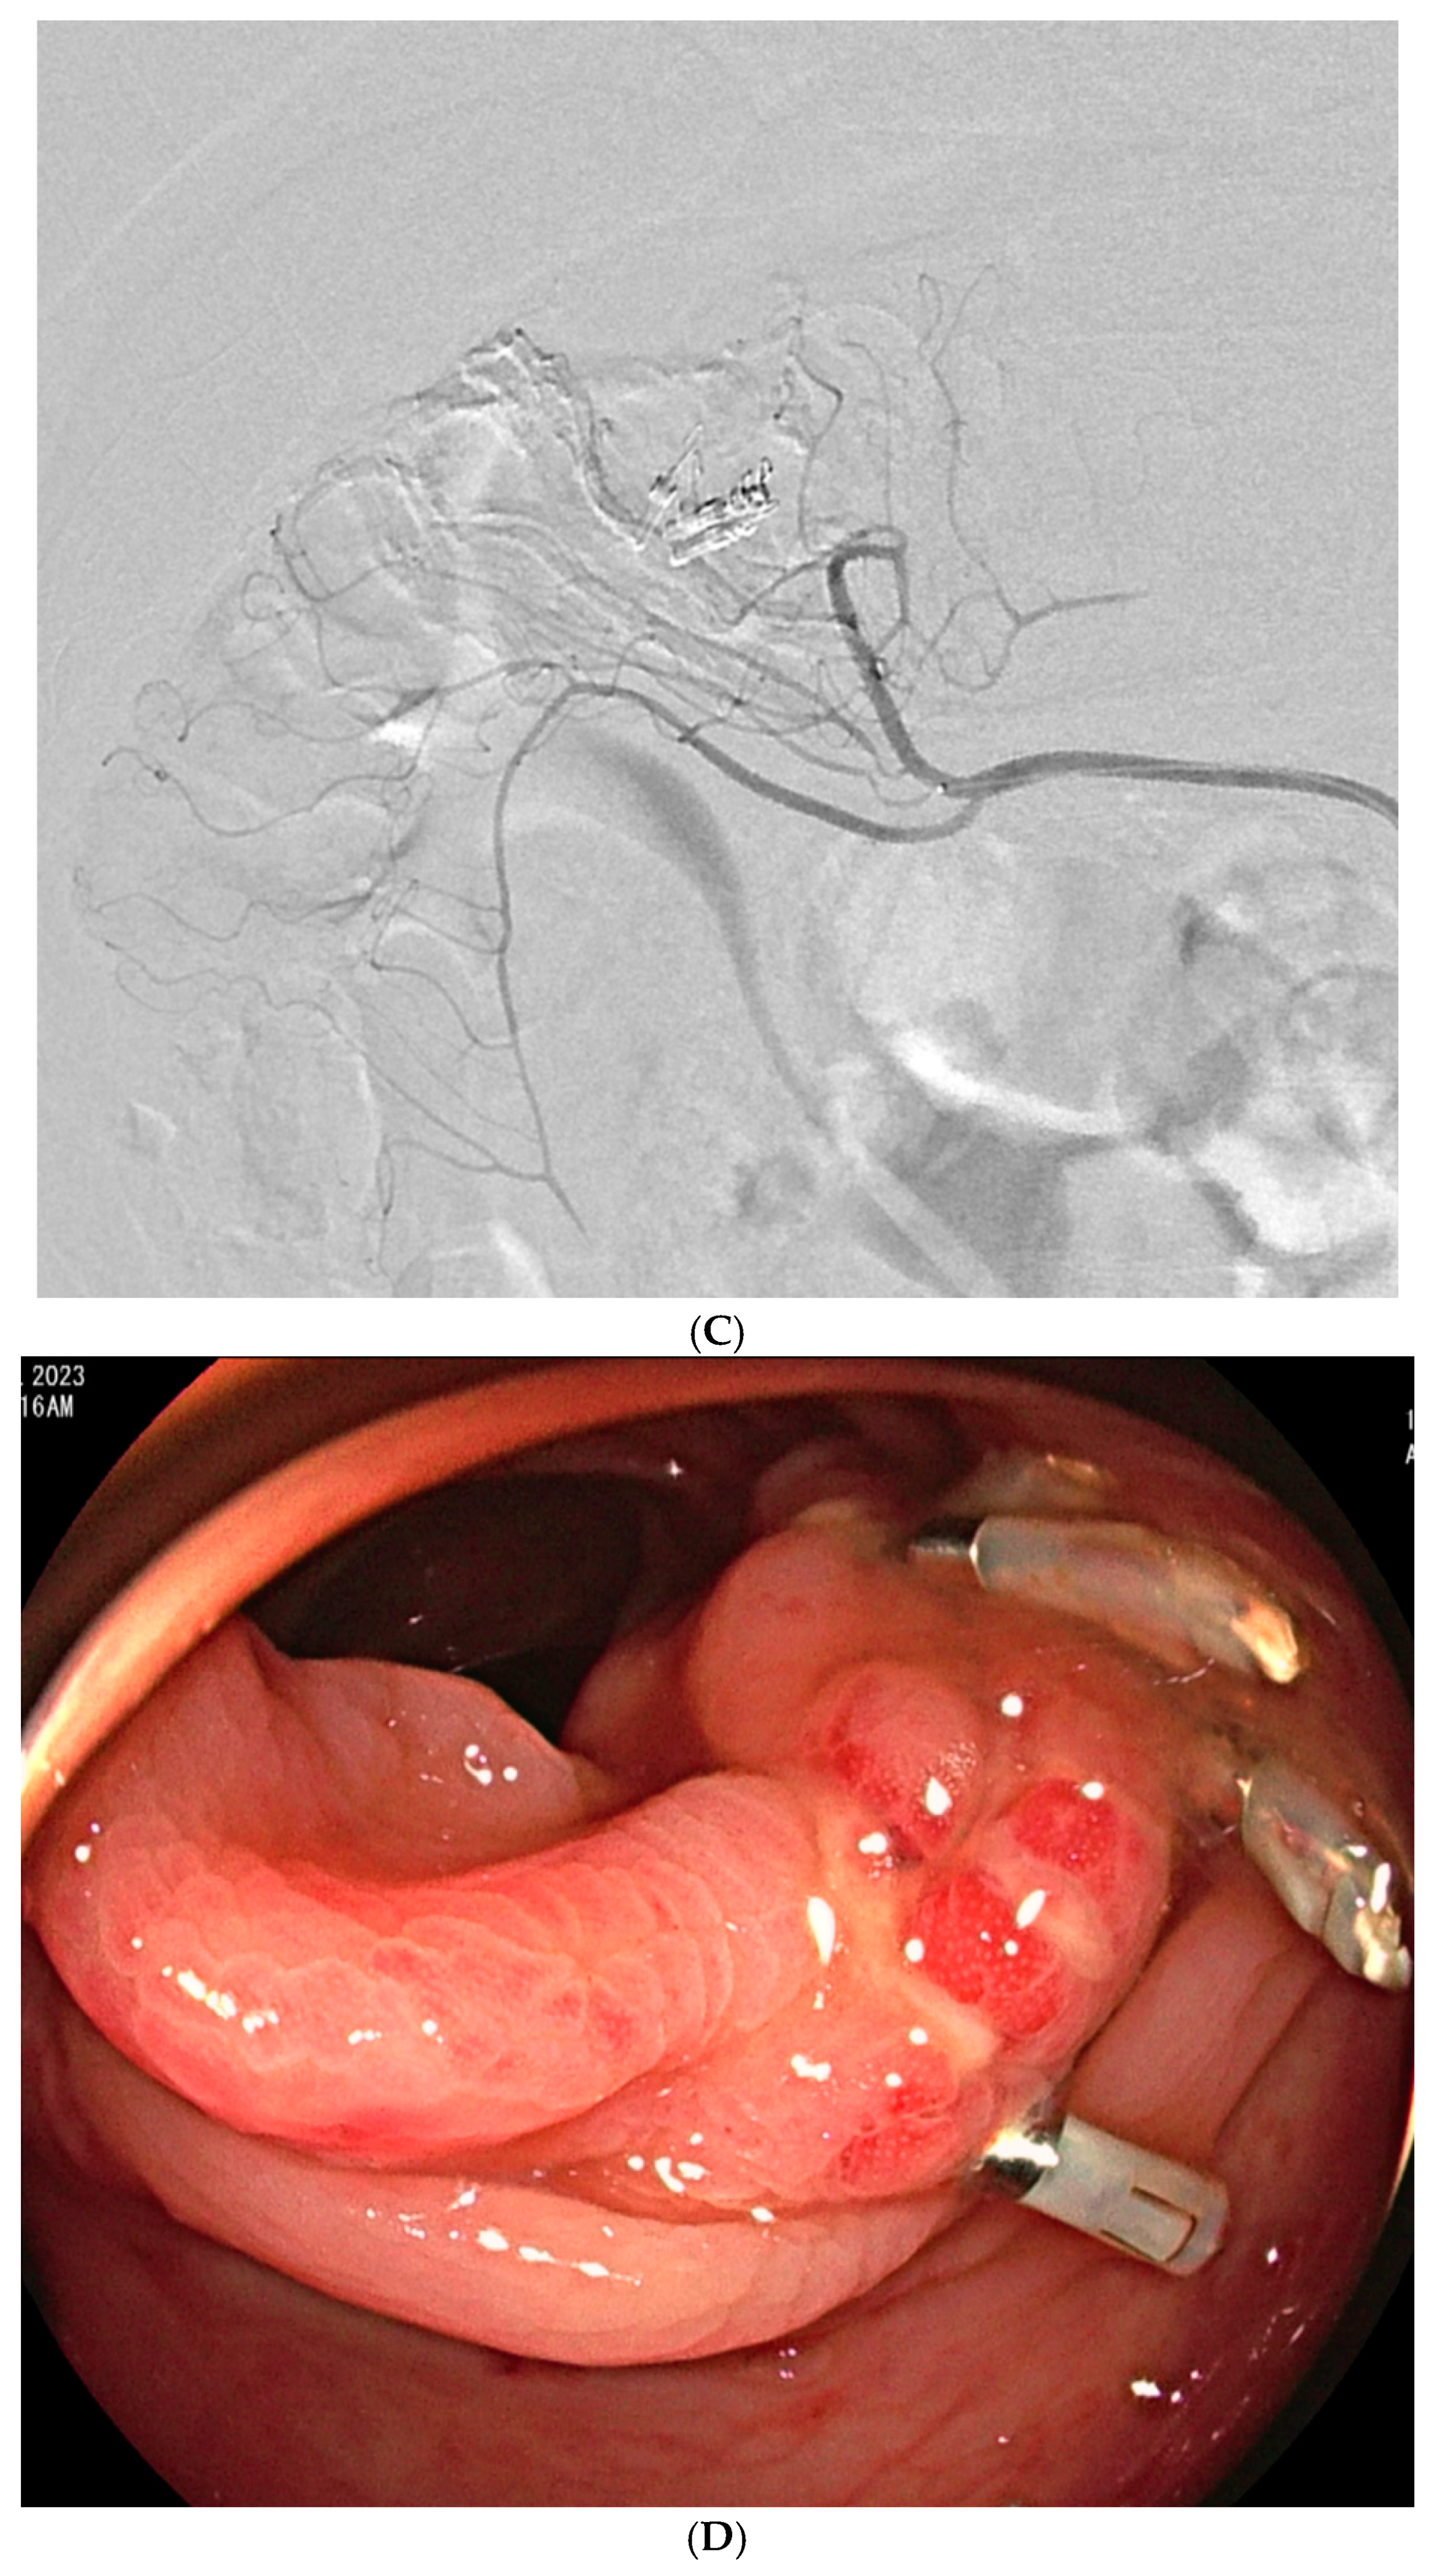

| No./Sex/Age | Bleeding Cause | Embolized Arteries | Angiography | Embolic Materials | Rebleeding Onset | Management | Remark |

|---|---|---|---|---|---|---|---|

| 1/F/81 | Lymphoma | Jejunal a. | Active bleeding | QS-GSPs (350–560 μm) | Persistent | Jejunal resection the next day | Improved |

| 2/F/72 | Uncertain | Ileal a. | Active bleeding | QS-GSPs (350–560 μm) | Persistent | TAE with NBCA | Improved |

| 3/F/49 | Diverticular bleeding | Cecal a. | No bleeding | QS-GSPs (350–560 μm) | 4 days later | Endoscopic clipping | Improved |

| 4/M/59 | Diverticular bleeding | Right colic a. | No bleeding | QS-GSPs (350–560 μm) | 2 days later | TAE with QS-GSPs | Improved |

| 5/M/70 | Colitis | Superior rectal a. | No bleeding | QS-GSPs (350–560 μm) | 5 days later | TAE with QS-GSPs and NBCA | Improved |

| 6/M/71 | Diverticular bleeding | Right colic a. | No bleeding | QS-GSPs (350–560 μm) | Persistent | Endoscopic clipping | Improved |

| 7/F/70 | Uncertain | Superior rectal a. | No bleeding | QS-GSPs (350–560 μm) | Persistent | No | Improved, transient ischemic colitis 1 day later |